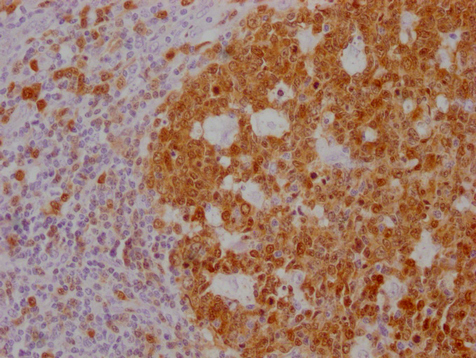

IHC image of CSB-MA181399 diluted at 1:100 and staining in paraffin-embedded human tonsil tissue performed on a Leica BondTM system. After dewaxing and hydration, antigen retrieval was mediated by high pressure in a citrate buffer (pH 6.0). Section was blocked with 10% normal goat serum 30min at RT. Then primary antibody (1% BSA) was incubated at 4°C overnight. The primary is detected by a Goat anti-mouse IgG polymer labeled by HRP and visualized using 0.05% DAB.